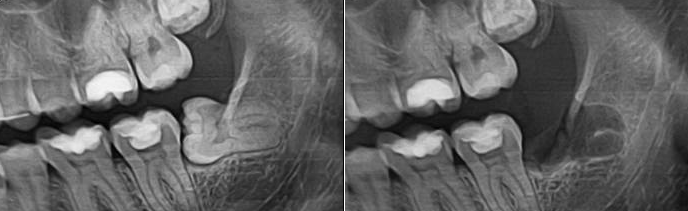

Удаление зубов: фото до и после